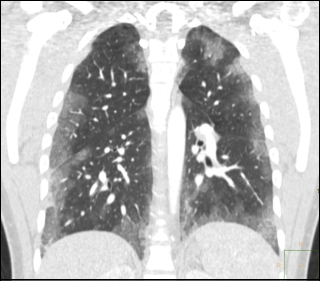

The doctors made a high resolution computed tomography scan [a sophisticated X-ray] of the man's lungs and saw haemorrhages everywhere. They are the white patches in the figure below.

Coughing blood during steroids cycle

The doctors assumed that the haemorrhages were the result of the injections of testosterone or nandrolone that the man had given himself. The steroids are dissolved in oil and have to be injected into muscle tissue. If the injected material enters the bloodstream by mistake, then oil can get into the lungs. And there the oil droplets cause bleeding to take place.